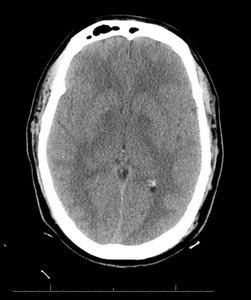

Further reevaluation of the patient’s initial head CT noted bilateral hypodensities in the globi pallidi (Figure 1). An MRI was ordered, revealing restricted diffusion on diffusion weighted imaging with symmetric bilateral involvement of the globi pallidi (GP). Hypointensity to surrounding brain parenchyma was noted on T1 Axial MRI, with corresponding hyperintensity on T2 Axial MRI. MRI films are included in this report (Figures 2 and 3). An arterial blood sample revealed a carboxyhemoglobin (COHb) level of 3.8% (above the absolute upper normal limit of 3% for smokers). Per his wife, the patient had smoked one to two packs of cigarettes daily for the past 18 years.

The GP, a deep subcortical structure at the inferior base of the brain, is the most frequently affected structure in CO poisoning and usually damaged immediately, symmetrically, and bilaterally.16 The leading theory for why CO specifically targets the GP is that it contains the highest iron content in the brain.17 The ischemic CO induced lesions in the bilateral GP of the basal ganglia can be seen as symmetric hypodensity on CT, hyperintensity on T2, hypointensity on T1, and restricted diffusion on diffusion weighted imaging MRI. The patient described in this case report demonstrated these classic findings on imaging that ultimately confirmed the diagnosis (Figures 1, 2, and 3).